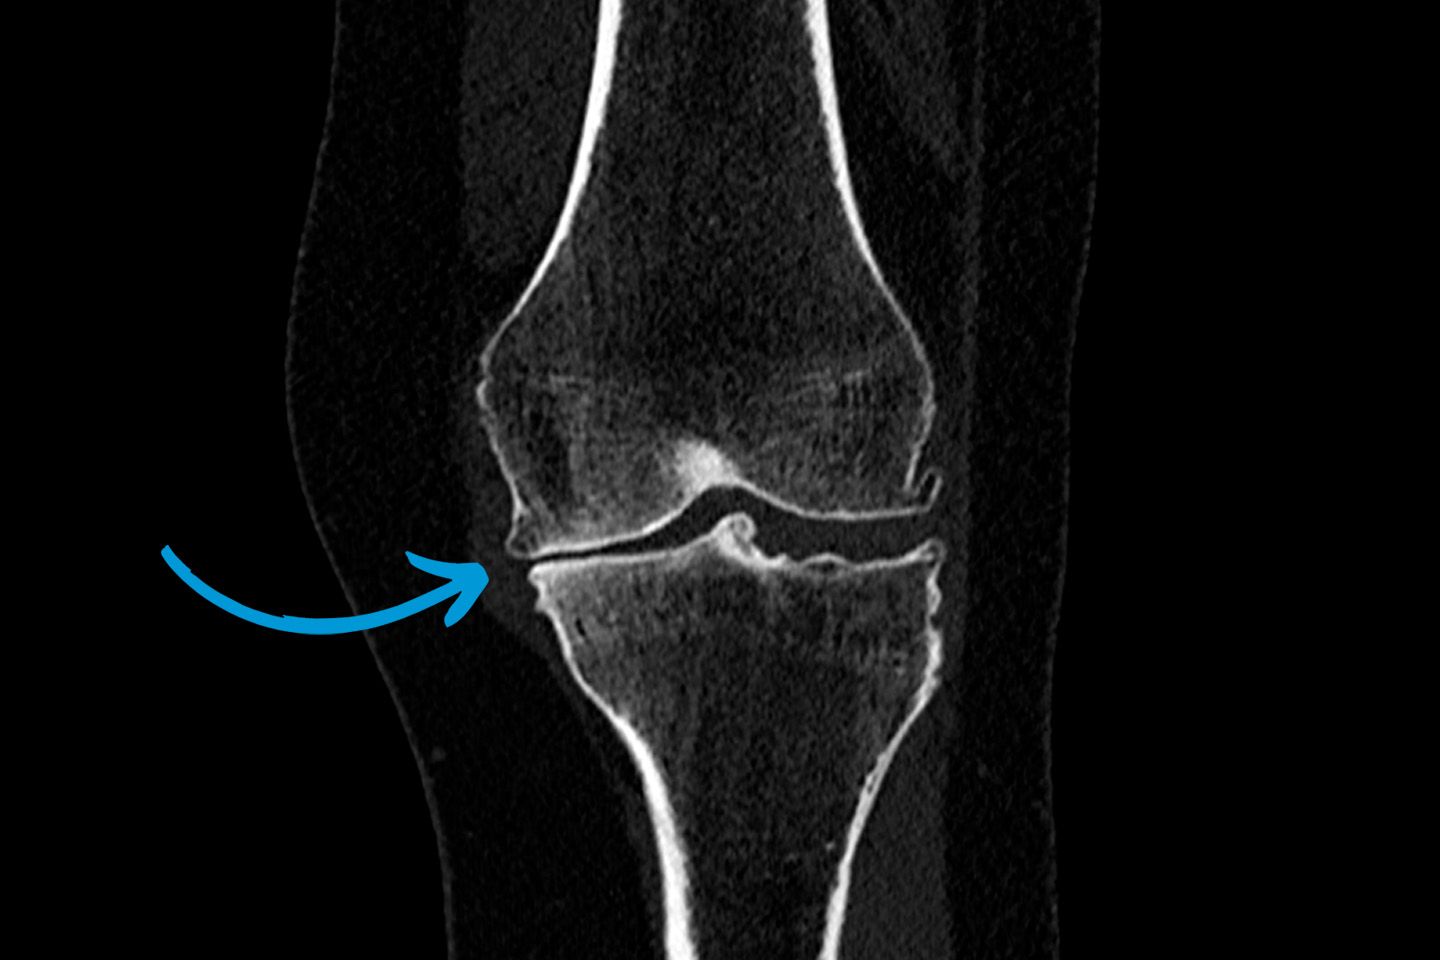

Schwere Arthrose des Kniegelenks mit aufgebrauchtem Gelenkspalt.

Durch den Einsatz moderner Verfahren wie Ultraschall, Röntgen, Magnetresonanztomographie (MRT) und Computertomographie (CT) können wir präzise Bilder des Bewegungsapparates erstellen. Diese ermöglichen es, die Ursachen von Beschwerden zu erkennen und gezielte Behandlungen einzuleiten. Dazu zählen Frakturen, Bänderverletzungen, Gelenkerkrankungen, degenerative Erkrankungen oder Tumorerkrankungen. Moderne Datenverarbeitung, wie die Integration von 3D-Bildgebung und hochauflösenden Techniken, gewährleistet präzise Diagnosen auf höchstem Niveau.